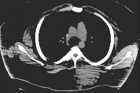

20 year old male presents after transfer to BGH with subtrochanteric left femur fracture

Zoom image: Radiological image Radiological image.

Zoom image: Cell stain Cell stain.